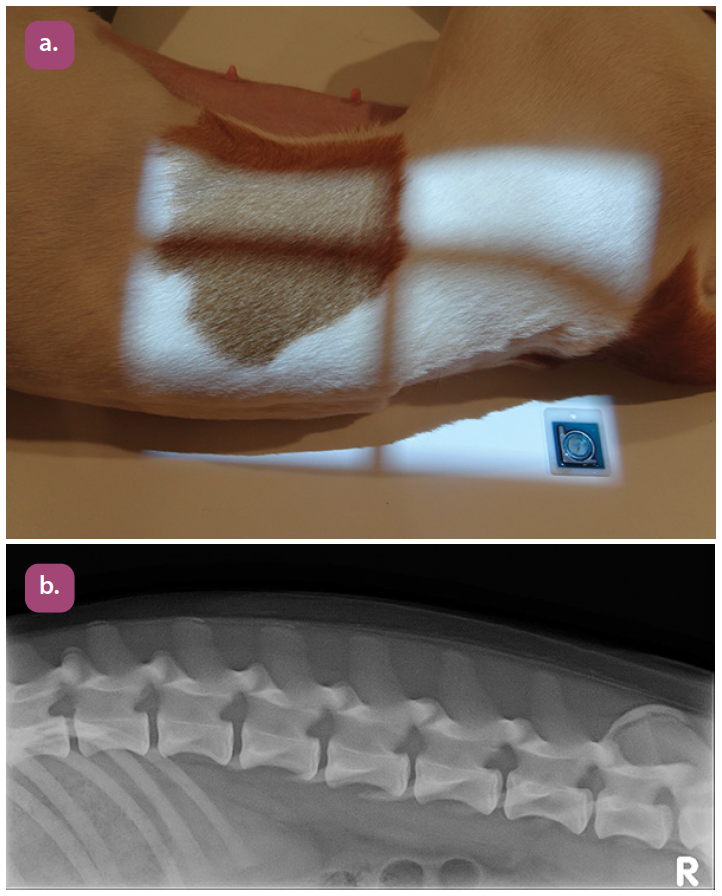

ventrodorsal lumbosacral projection

lateral lumbosacral projection